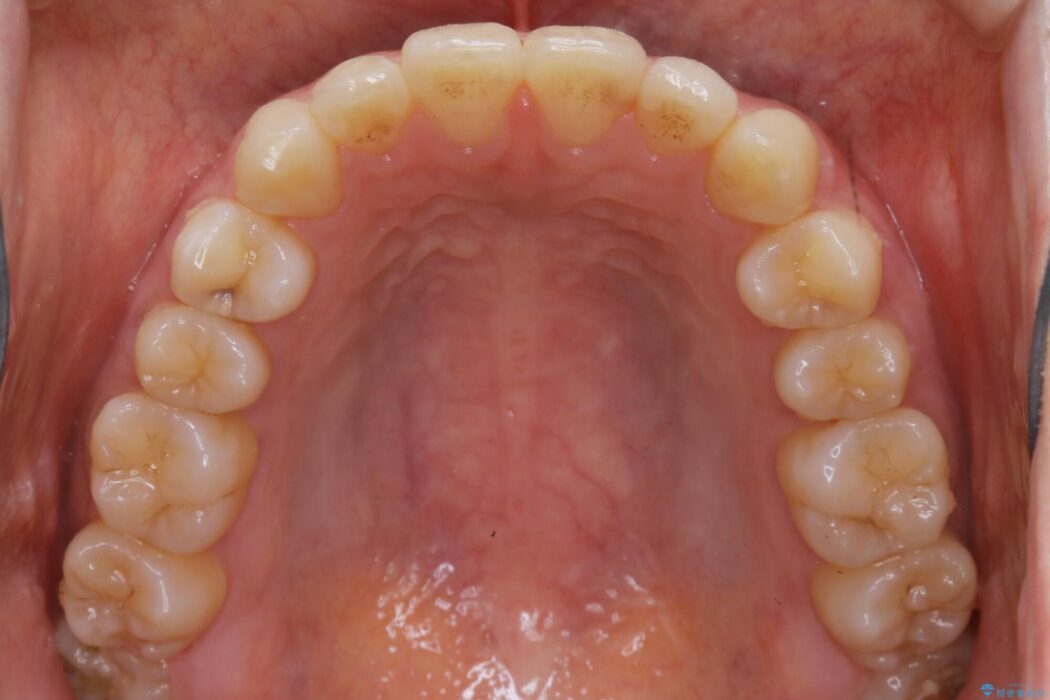

下の前歯のガタつきが気になるとご来院された患者様です。

インビザラインのライトパッケージにて、歯列拡大とディスキング(IPR)をを行いスペースをつくり非抜歯で治療を行いました。

歯列弓の拡大

歯並びが悪くなる原因の一つに「歯列弓の狭窄」というものがあります。

奥歯や前歯が内側(舌側)に倒れ込んでしまったり、歯が生えてくる位置が内側になってしまうことにより歯並びのアーチが狭くなってしまうことを言います。

このような場合、歯並びのアーチを拡大してあげるだけでもガタつきを無くすためのスペースがかなり作れることがあります。